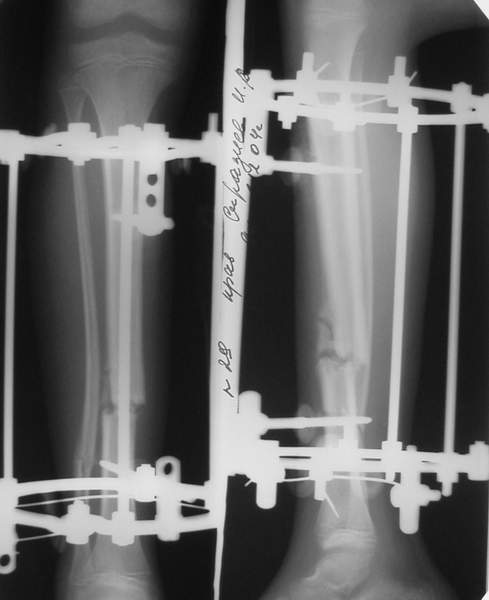

2

3a

3b

3c

В аттачте № 3 - один из примеров полукольцевого аппарат...

Это уже я баловался.

Итог? Работы больше (по времени и

интраоп "подгонке"), срастается также, а особого преимущества по сравнению с

"чиста" кольцевым (вес, удобство ношения и пр.) - я, по крайней мере,

не нашел.

Теперь не балуюсь.